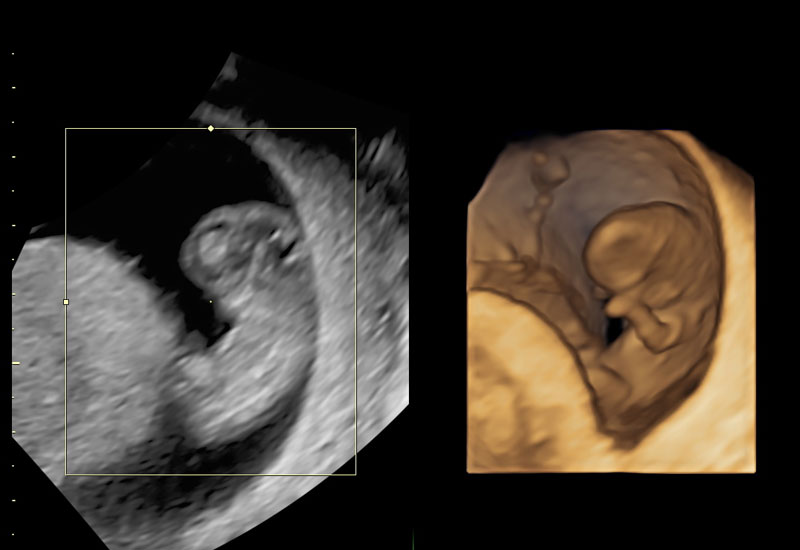

Early Pregnancy Scan

The Early Pregnancy Scan is an important ultrasound examination performed in the first few weeks of pregnancy. It provides reliable confirmation of pregnancy, ensures the baby is developing in the correct location, and helps establish accurate dates. Under the expertise of Dr. Ashwini Rathi, this scan offers both medical reassurance and emotional comfort during the earliest stages of pregnancy.

The Early Pregnancy Scan is usually performed between 6 to 9 weeks of pregnancy. At this stage, important structures like the gestational sac, yolk sac, and fetal heartbeat can be clearly seen.

What does the scan assess?

- Confirmation of pregnancy within the uterus

- Detection of fetal heartbeat

- Number of embryos (single or multiple pregnancy)

- Accurate dating of pregnancy

- Assessment of uterus and ovaries

- Early detection of ectopic or abnormal pregnancy